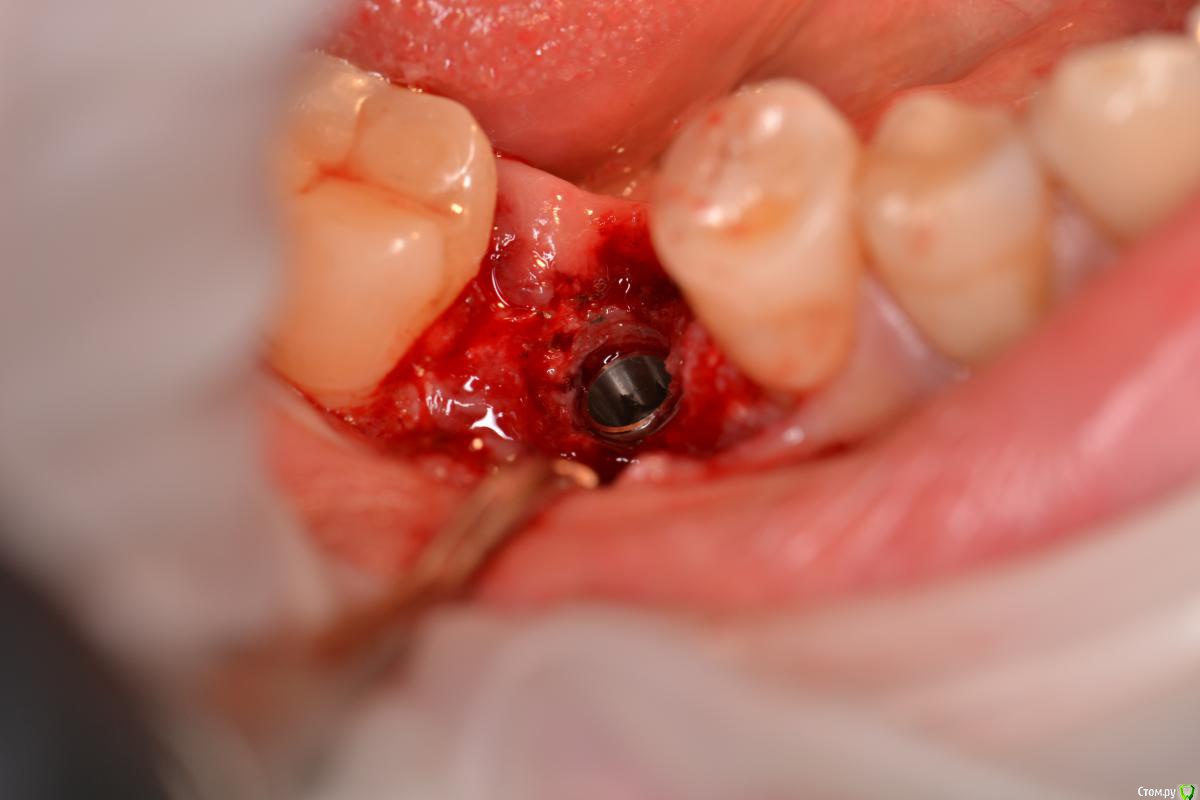

TIGER Опубликовано 22 декабря, 2016 Поделиться Опубликовано 22 декабря, 2016 Если вам сегодня нравится,что вы сделали вчера ,то вы стоите на месте....)Имплант ставил я, с виду по первому фото видно,что вроде-бы ничего...но на тот момент я бы был удовлетворён результатом,да он интегрирован,пациент доволен,отпротезировал бы,но сегодня нет...зондирование выявило резорбцию....и главное я знал,что прогноз не очень,эстетика и жизнь этого болтика...настоял на удалении...сегодня заказал набор,и на выход,сразу же имплант,заглубил,как надо)Как говорил если мне не изменяет память Эдуард Анчаков наступает эра вынимайзинга....начал со своего)P.S какое приятное чувство когда ты можешь исправить свои недочёты) 3 Ссылка на комментарий

TIGER Опубликовано 22 декабря, 2016 Автор Поделиться Опубликовано 22 декабря, 2016 Почему такое могло произойти,есть снимки после установки?Недозаглубил...банально...Снимка нет Ссылка на комментарий

Тимур86 Опубликовано 23 декабря, 2016 Поделиться Опубликовано 23 декабря, 2016 как недозаглубление вызывает такую сильную резорбцию? 5 Ссылка на комментарий

TIGER Опубликовано 24 декабря, 2016 Автор Поделиться Опубликовано 24 декабря, 2016 как недозаглубление вызывает такую сильную резорбцию?несколько факторов в купе... Ссылка на комментарий